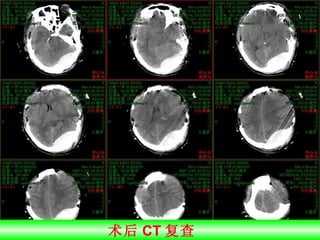

术后 CT 复查

直切口手术

再次术后亚低温治疗